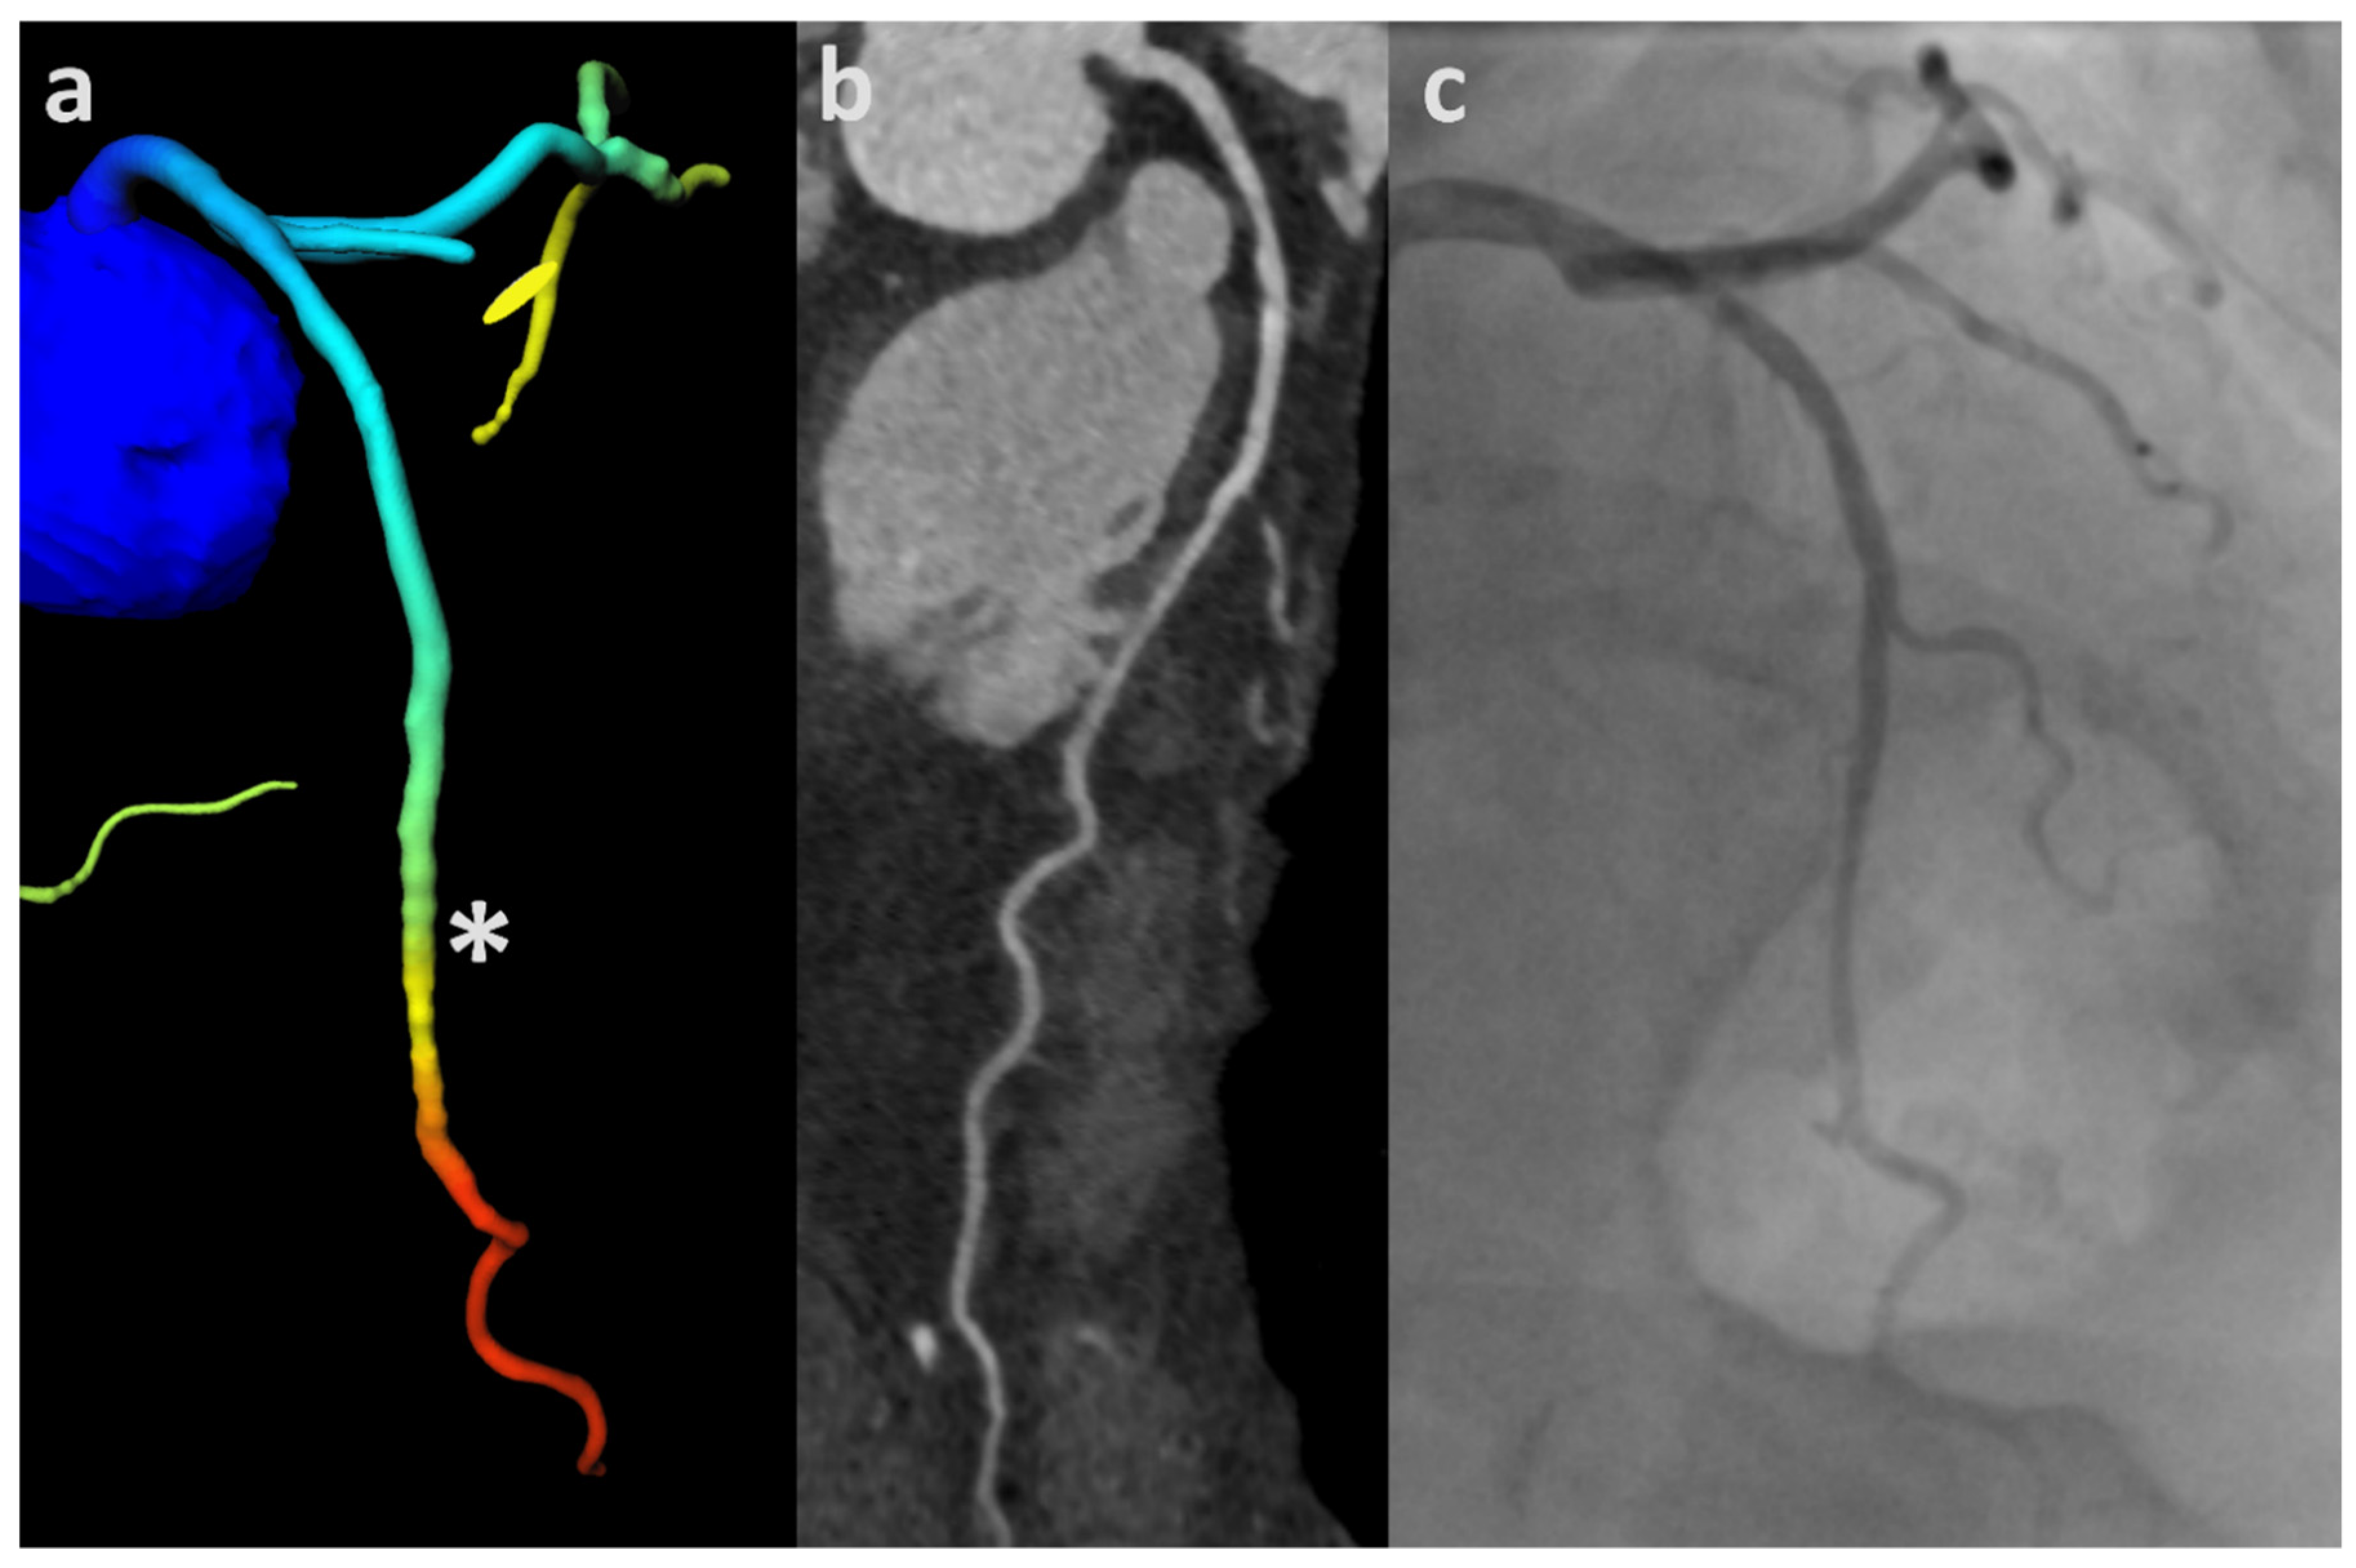

2.5. CT-FFR